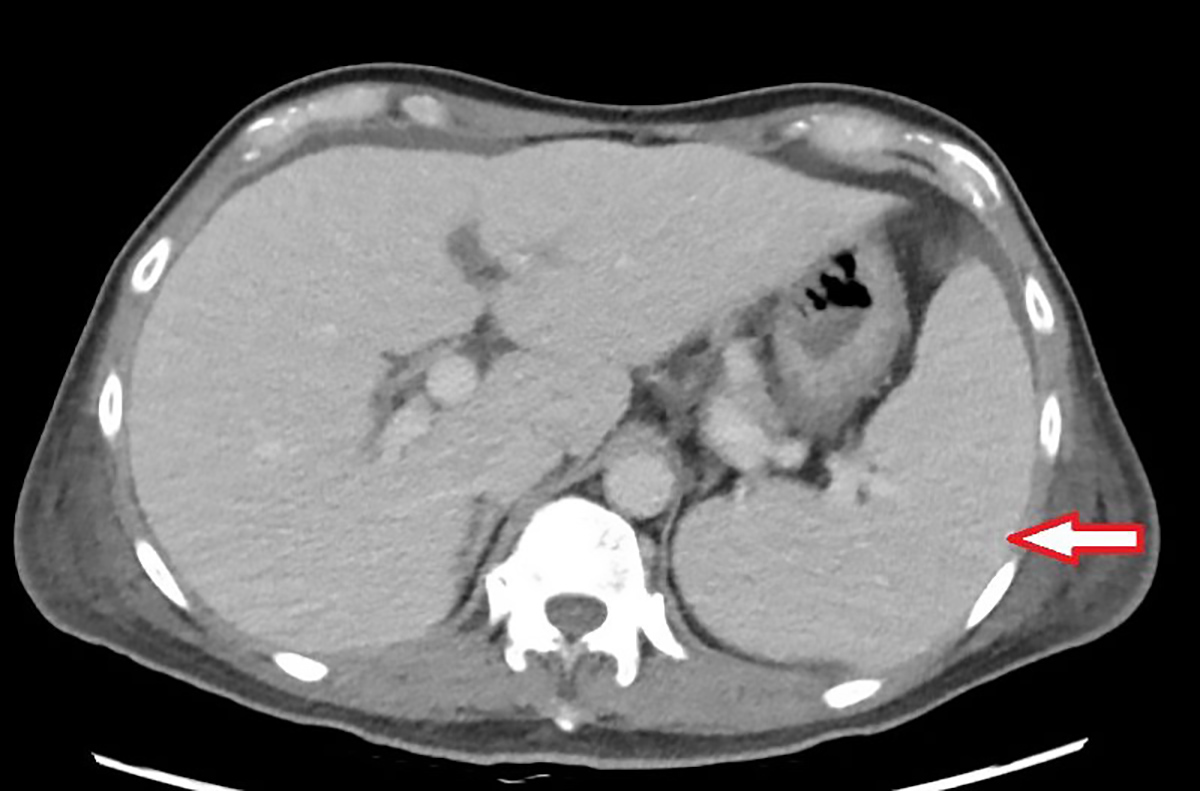

63歲的林先生去年底開始出現不明原因的反覆高燒,多次奔波診所與各大科別求診,卻始終找不到原因,因而來到台北慈濟醫院感染科就醫。抽血檢查顯示白血球、血小板及血紅素低下,必須輸血,但血液及骨髓等相關檢查均找不到病因,僅電腦斷層意外發現脾臟腫大與腹水。最後在住院的心臟超音波檢查中發現林先生罹患三尖瓣重度閉鎖不全,瓣膜上還長了一公分大的贅生物(即細菌感染的病灶),確診為感染性心內膜炎。會診心臟血管外科後,楊凱文醫師替其更換人工生物瓣膜,術中同步清除感染病灶。手術出院後,門診經過一段時間的追蹤,病人的血球數值明顯回升,感染也治療完全,順利恢復健康。

三尖瓣是位於心臟右心房與右心室之間的重要瓣膜,負責讓血液從右心房單向流入右心室,防止血液倒流,功能上與左心房和左心室之間的二尖瓣類似。楊凱文醫師指出,造成三尖瓣逆流的原因繁多,包括風濕性心臟病、感染性心內膜炎、二尖瓣或主動脈瓣疾病、心律不整,甚至是長期抽菸、慢性呼吸道疾病、自體免疫疾病均可能導致三尖瓣逆流。若三尖瓣功能受損,血液逆流回右心房,使右心房壓力增加,進而影響全身血液回流,就會導致器官壓力上升,當逆流非常嚴重且延遲治療,少部份病人甚至可能導致肝脾出現問題,如肝硬化、脾臟腫大等。而脾臟是造血器官,若因此腫大造成血球細胞破壞,就可能導致全身性血球減少,發生如林先生一般的情況。